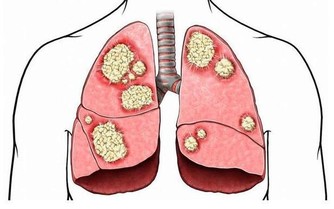

據統計,約有22%的素食者會得脂肪肝,而這些人也大多是正常體型。劉曉光醫師稱,人體中所需要的能量主要來自三大營養物質,脂肪、蛋白質和碳水化合物。像陳先生這種純素食者,不吃魚肉蛋等營養物質,也就是少了動物蛋白質和脂肪來源,人體的白蛋白合成減少,就需要分解脂肪組織來維持營養均衡,大量的脂肪酸從脂肪組織中釋放進入肝臟后,而這種脂肪在肝臟中不易被分解,若不能及時排出,肝臟中的脂肪堆積過多,長期以往,就形成了脂肪肝。

不只是素食主義者有患病隱患,曾經有社區在湖北武漢對歸元寺、鐵佛寺的兩寺僧人進行體檢,結果令人大吃一驚:受檢的30名僧人中,接近一半的僧人的肝內總脂肪量佔到肝重的5%-10%,達到輕度脂肪肝的標準。